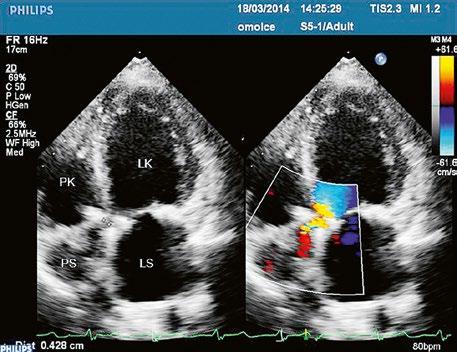

Poslechový nález systolického šelestu nad plicnicí s fixním rozštěpem 2. ozvy je nenápadný. Echokardiograficky je patrná dilatovaná a objemově přetížená pravá komora s paradoxním pohybem septa (Obr. 45.9), zkratový tok může být vidět i transtorakálně (TTE) (Obr. 45.10, Video 45.3, Video 45.7), ale suverénní diagnostickou metodou je jícnová echokardiografie (TEE), případně s 3DE zobrazením (Obr. 45.1, Obr. 45.2,

Obr. 45.10 TTE, čtyřdutinová apikální projekce s levo pravým zkratem na úrovni síní (šipka) při defektu septa síní typu secundum PK – pravá komora, LK – levá komora, LS – levá síň, PS – pravá síň